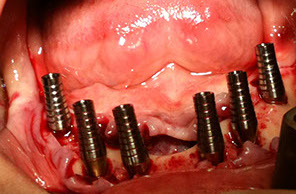

implantologia con carico immediato su 6 impianti

L’implantologia dentale è quella disciplina che consente il recupero della masticazione e e dei denti mancanti attraverso l’utilizzo di radici artificiali in titanio dette: impianti endossei

Il titanio è il materiale piu biocompatibile attualmente in uso.

L’implantologia dentale è una tecnica sicura e la percentuale di successo è superiore al 98%.

L’implantologia dentale può anche essere eseguita a carico immediato. Il carico immediato consiste nelᅠcontestuale posizionamento di un dente provvisorio lo stesso giorno dell’intervento. L’opportunità di eseguire un carico immediato è valutata caso per caso, qualora se ne presentino le condizioni necessarie.